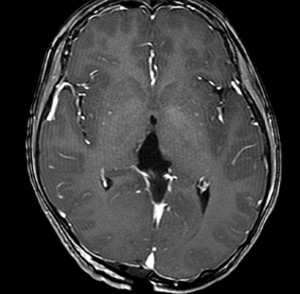

CTです

左のCTでは低密度の松果体腫瘍とまばらな石灰化がみられます。右の造影CTでは,腫瘍のごく一部が増強されます。 この時点で,低吸収で石灰化があるので類皮のう胞 dermoid cystを強く疑います。dermoid cystを主体とする混合性胚細胞腫瘍 mixed germ cell tumorも候補です。あるとすれば,germinomaかteratomaです。